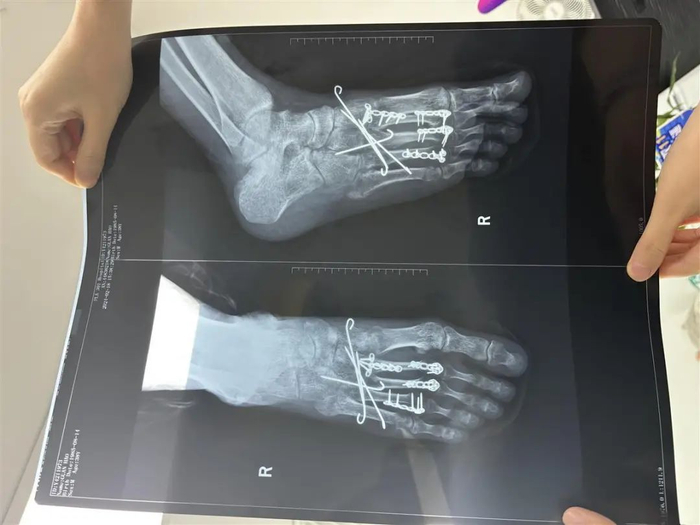

关先生当晚被送往罗湖区人民医院治疗,后转到北京的医院。根据医院诊断,关先生“右足第2、3、4跖骨骨折”,关先生的右脚被植入4块钢板和4根钢钉。经过近10个月的恢复,关先生走路还需要依靠拐杖。